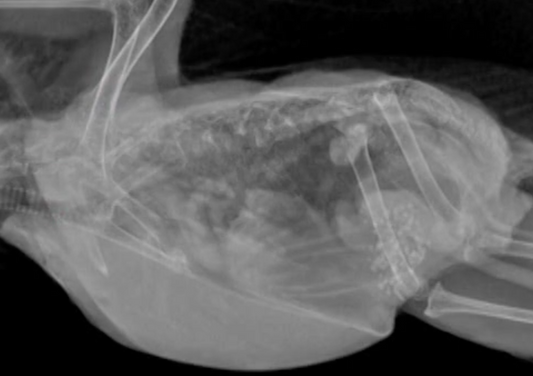

Collection: Avian